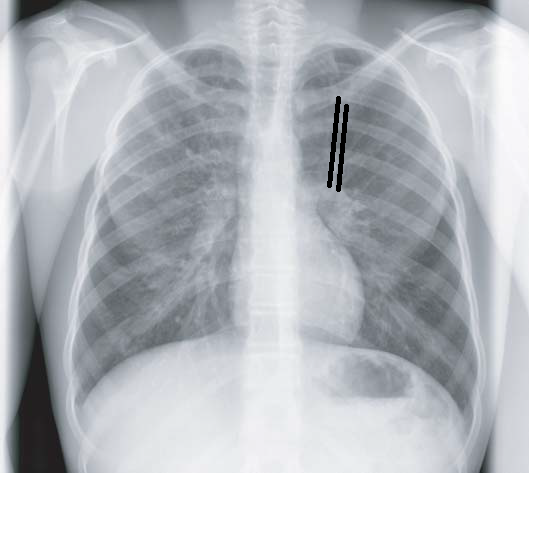

Chest X Ray For Bronchiectasis . Chest ct scan if indicated (e.g., hemoptysis, or concern for pulmonary. Chest radiography is usually the initial study performed in suspected bronchiectasis. This guideline provides recommendations and good practice points for the diagnosis and management of bronchiectasis in adults. Chest radiography is usually the first imaging examination, but the findings are often nonspecific, and the images can appear normal. Shows bronchial dilation, with or without airway thickening. Diagnosis of bronchiectasis is usually made using chest computed tomography (ct) scan, the current gold standard method. In addition to making the diagnosis, the pattern of. Signs in severe disease include tram lines and ring shadows. Required to exclude other pathologies. A bronchiectatic airway can show abnormal widening and thickening of its airway wall. In addition, it can show an irregular wall and lack of tapering, and/or can be visible in the periphery of the lung.

Chest X Ray For Bronchiectasis Shows bronchial dilation, with or without airway thickening. Chest radiography is usually the initial study performed in suspected bronchiectasis. Chest radiography is usually the first imaging examination, but the findings are often nonspecific, and the images can appear normal. In addition to making the diagnosis, the pattern of. Required to exclude other pathologies. Signs in severe disease include tram lines and ring shadows. Diagnosis of bronchiectasis is usually made using chest computed tomography (ct) scan, the current gold standard method. Shows bronchial dilation, with or without airway thickening. In addition, it can show an irregular wall and lack of tapering, and/or can be visible in the periphery of the lung. Chest ct scan if indicated (e.g., hemoptysis, or concern for pulmonary. This guideline provides recommendations and good practice points for the diagnosis and management of bronchiectasis in adults. A bronchiectatic airway can show abnormal widening and thickening of its airway wall.

Chest Medicine Made EasyDr Deepu The Rings !!!The Trams!!!, Chest X Chest X Ray For Bronchiectasis This guideline provides recommendations and good practice points for the diagnosis and management of bronchiectasis in adults. Signs in severe disease include tram lines and ring shadows. In addition, it can show an irregular wall and lack of tapering, and/or can be visible in the periphery of the lung. Chest radiography is usually the first imaging examination, but the findings. Chest X Ray For Bronchiectasis.

Bronchiectasis Chest X Ray Chest X Ray For Bronchiectasis A bronchiectatic airway can show abnormal widening and thickening of its airway wall. Chest radiography is usually the initial study performed in suspected bronchiectasis. Chest radiography is usually the first imaging examination, but the findings are often nonspecific, and the images can appear normal. Signs in severe disease include tram lines and ring shadows. Diagnosis of bronchiectasis is usually made. Chest X Ray For Bronchiectasis.